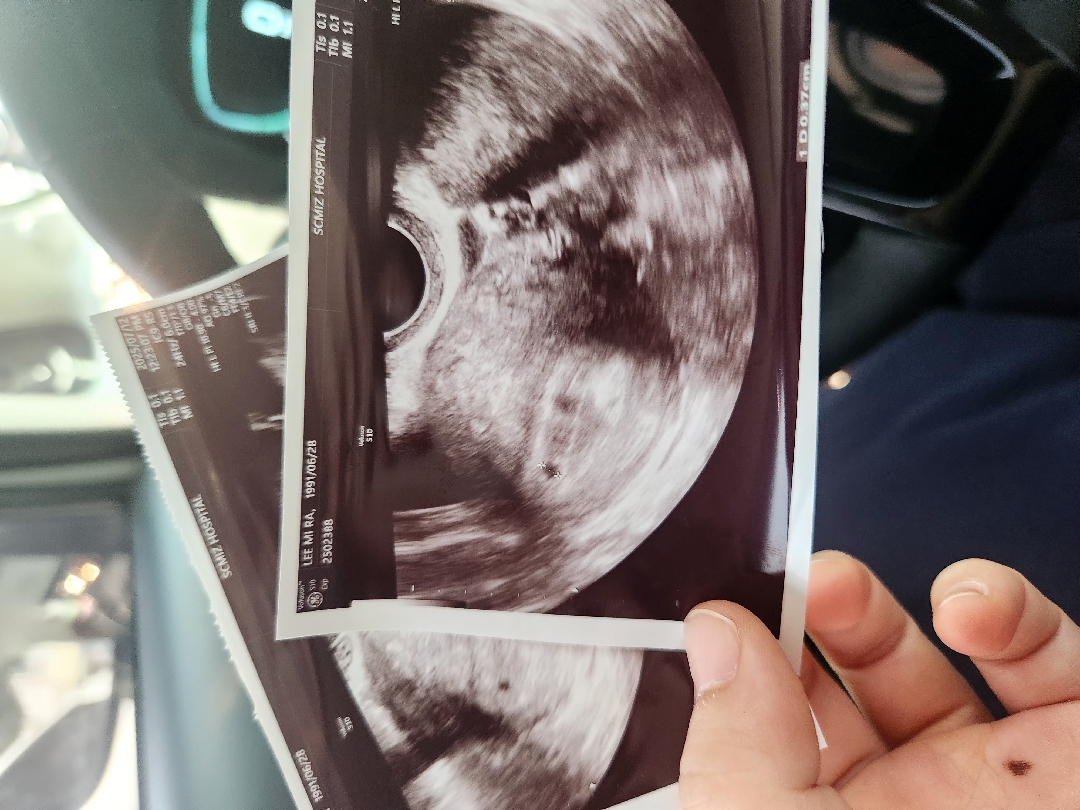

5w1d

0.37cm 너무너무 작은 아이가 뱃속에서 자라고있다 잘 자라야할텐데 난황볼수있을까 기대했지만 아기집 보고온걸로 만족해야겠당